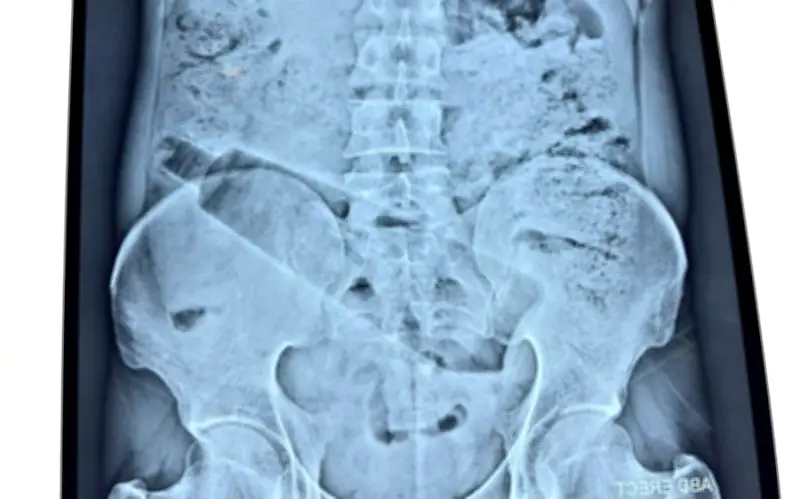

Người đàn ông 38 tuổi, cư trú tại khu Saket Colony, đã trải qua cơn đau bụng dữ dội kéo dài gần 36 giờ trước khi được đưa đến một bệnh viện tư nhân để điều trị. Sau khi thăm khám lâm sàng và tiến hành chụp X-quang, các bác sĩ phát hiện một chai nhựa dung tích một lít bị mắc kẹt bên trong cơ thể ông, cụ thể là ở vùng trực tràng. Phát hiện này đã làm nổi bật mức độ nghiêm trọng của tình trạng và yêu cầu can thiệp phẫu thuật khẩn cấp.